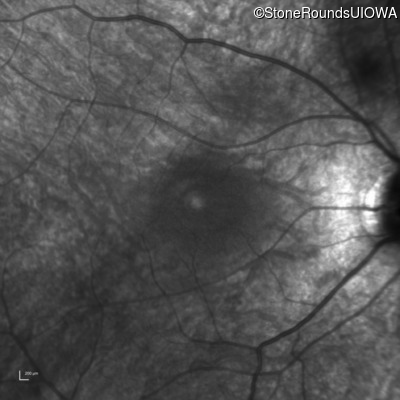

Infrared Fundus Photograph - Right - 20/60

Exemplar

Infrared Fundus Photograph - Left - 20/70